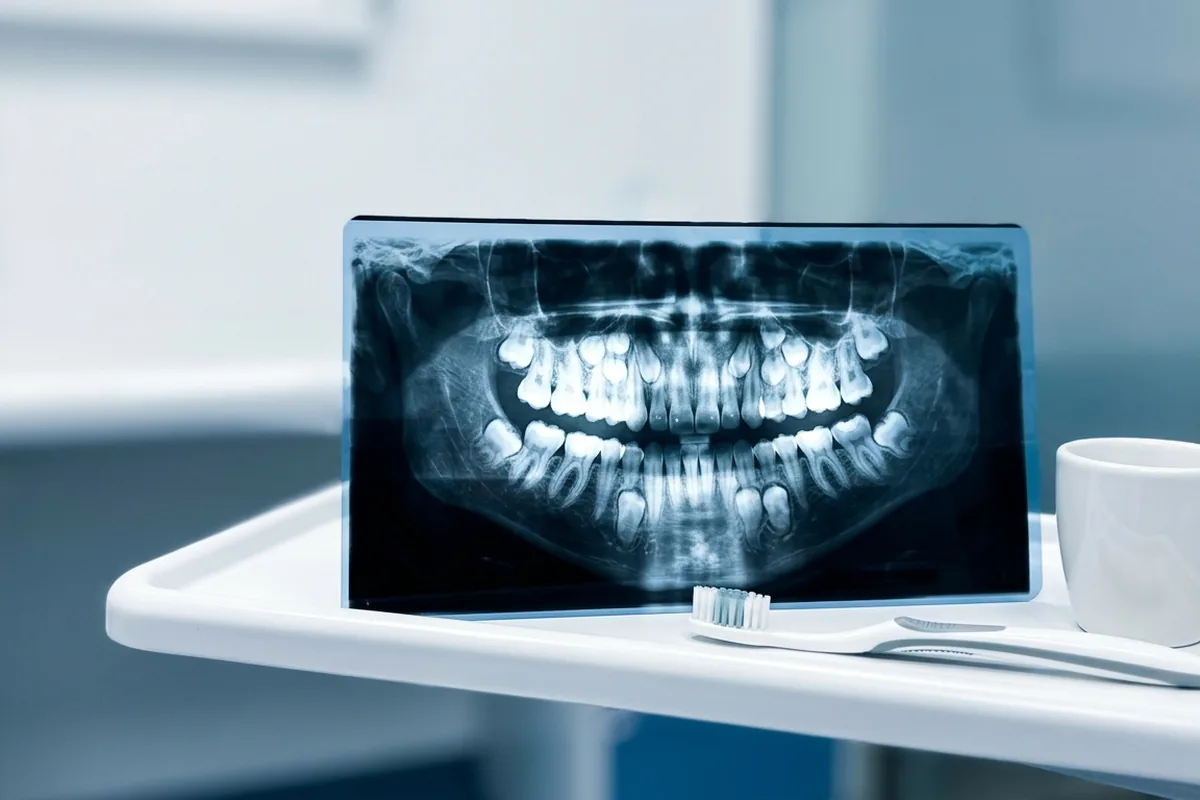

Po wykonaniu szczegółowych badań i zdjęć rentgenowskich, stało się jasne, że Kumar jest medycznym ewenementem. Oficjalna komisja Księgi Rekordów Guinnessa potwierdziła, że mężczyzna posiada największą liczbę zębów u człowieka na świecie.

Większość z nas posiada 32 zęby, wliczając w to tzw. zęby mądrości. W przypadku Kumara dodatkowe uzębienie nie sprawiało mu bólu ani dyskomfortu, co jest niezwykle rzadkie przy tak dużej liczbie nadliczbowych jednostek. Po prostu natura postanowiła obdarzyć go „podwójnym” uśmiechem.